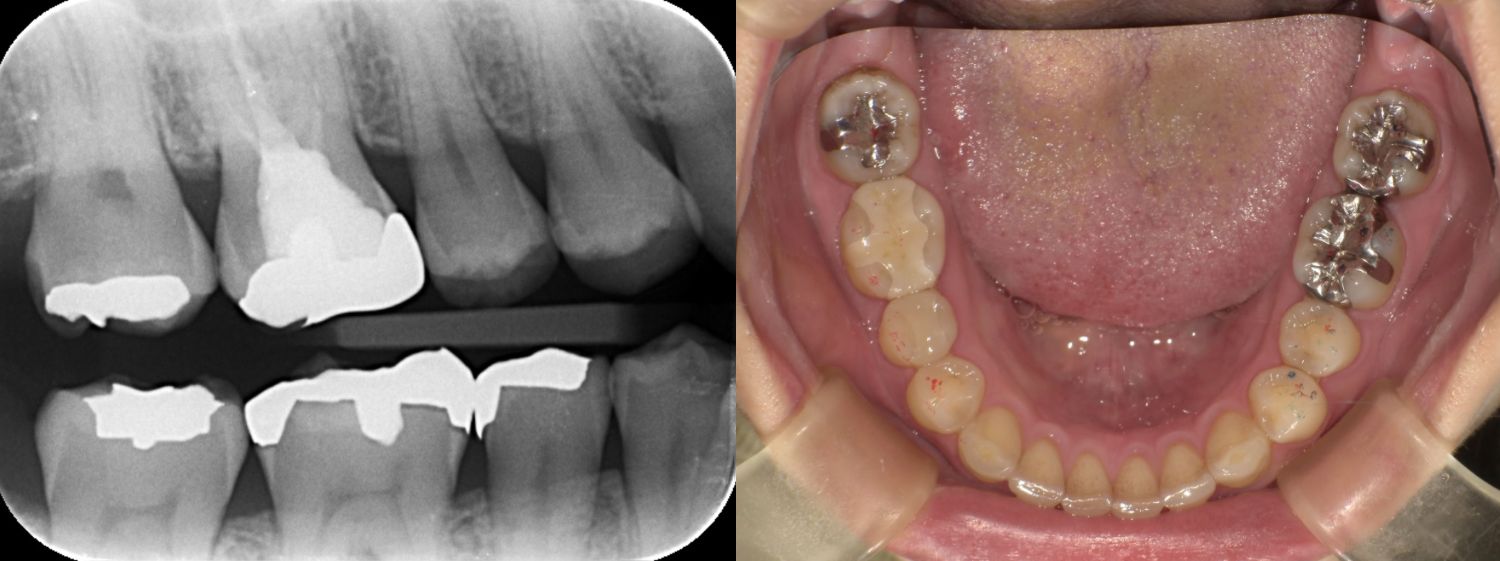

①術前

左上7はう蝕を取り除き1時間でセラミック修復を行った。

| 診断 | ①右上4う蝕 ②左上67う蝕 ③左下67う蝕 |

| 処置内容 (または主訴) | ①セレックインレー ②右上6セレックインレー 右上7CR ③セレックインレー |